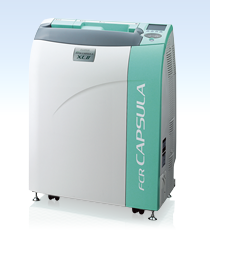

Como o nome indica, CAPSULA, que significa caixa pequena em latim, foi drasticamente dimensionada para ser menor e mais leve do que nunca. Com o método revolucionário de carregamento do cassete vertical da FUJIFILM, o espaço de trabalho foi reduzido em comparação com os modelos de inserção horizontal anteriores, sem comprometer a velocidade ou qualidade da imagem.

O processamento da FCR CAPSULA X de 43-72 imagens por hora é ideal para áreas de volume baixo ou remoto com um fluxo de trabalho menos exigente.